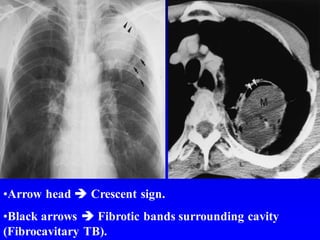

•Arrow head  Crescent sign.

•Black arrows  Fibrotic bands surrounding cavity

(Fibrocavitary TB).